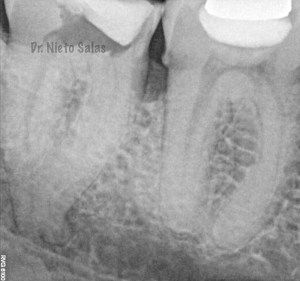

La otra pieza, el 3.7, se instrumentó con sistema Protaper y obturación con Ola continua de Calor y un back-filling con la pistola Obtura II.

(buscamos siempre algún conducto lateral, para intentar asegurarnos de su limpieza)

Y una en las demás proyecciones MESIO Y DISTO: